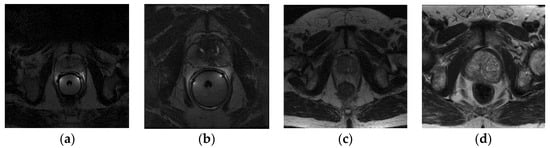

The PROMISE12 dataset comes from four different medical centers, and it includes both patients with benign disease (e.g., benign prostatic hyperplasia) and prostate cancer. It contains 80 available T2-weighted axial MR images of the prostate, 50 of which have expert segmentation masks while the remaining 30 do not. The in-plane image size varies from 256 × 256 to 512 × 512 pixels. In MRI images, the pixel/voxel intensities and appearance characteristics of the prostate can significantly depend on different acquisition protocols and scanners. Table 1 lists the details of the dataset, and Figure 1 shows one sample scan from each center.

Figure 1. Example image slices from PROMISE12 dataset; (a) 1.5 T with ERC from HK; (b) 3.0 T with ERC from BIDMC; (c) 1.5 T without ERC from UCL; (d) 3.0 T without ERC from RUNMC.